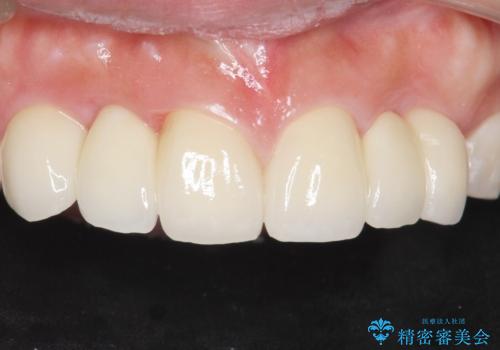

自然な仕上がりにご満足頂けました。

治療終了後、奥歯に残っていた矯正の接着剤を除去し、ホワイトニングも行いました。

クラウンの種類:オールセラミッククラウン スタンダード